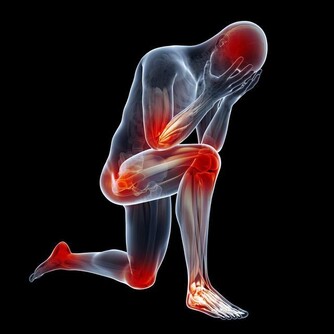

醫師建議乾癬患者務必注意關節症狀,像是早上起床,

關節紅腫脹痛特別明顯的人最好趕緊就醫,以免惡化至關節變形,造成不可挽回的悲劇。

2. 好發頭皮與肘膝:乾癬最常發生在頭皮、手肘、膝蓋等部位,

因為頻繁摩擦,導致皮膚會紅、變厚,而且有屑屑。